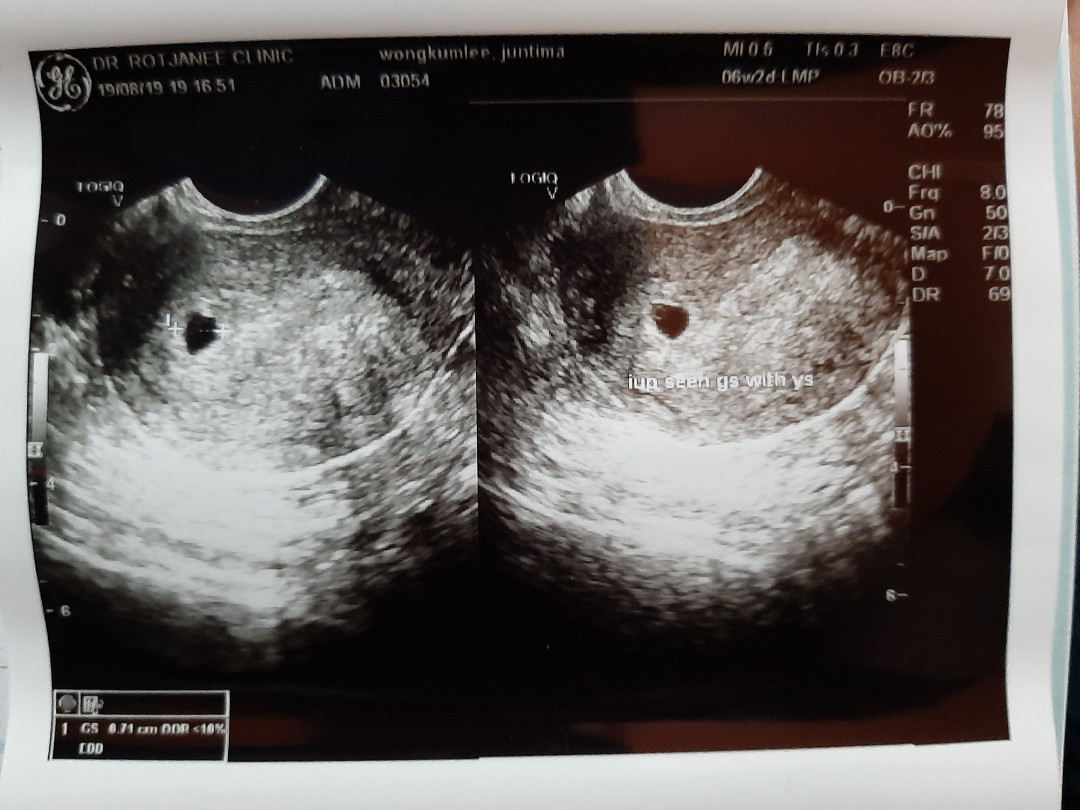

6w2d ค่ะ